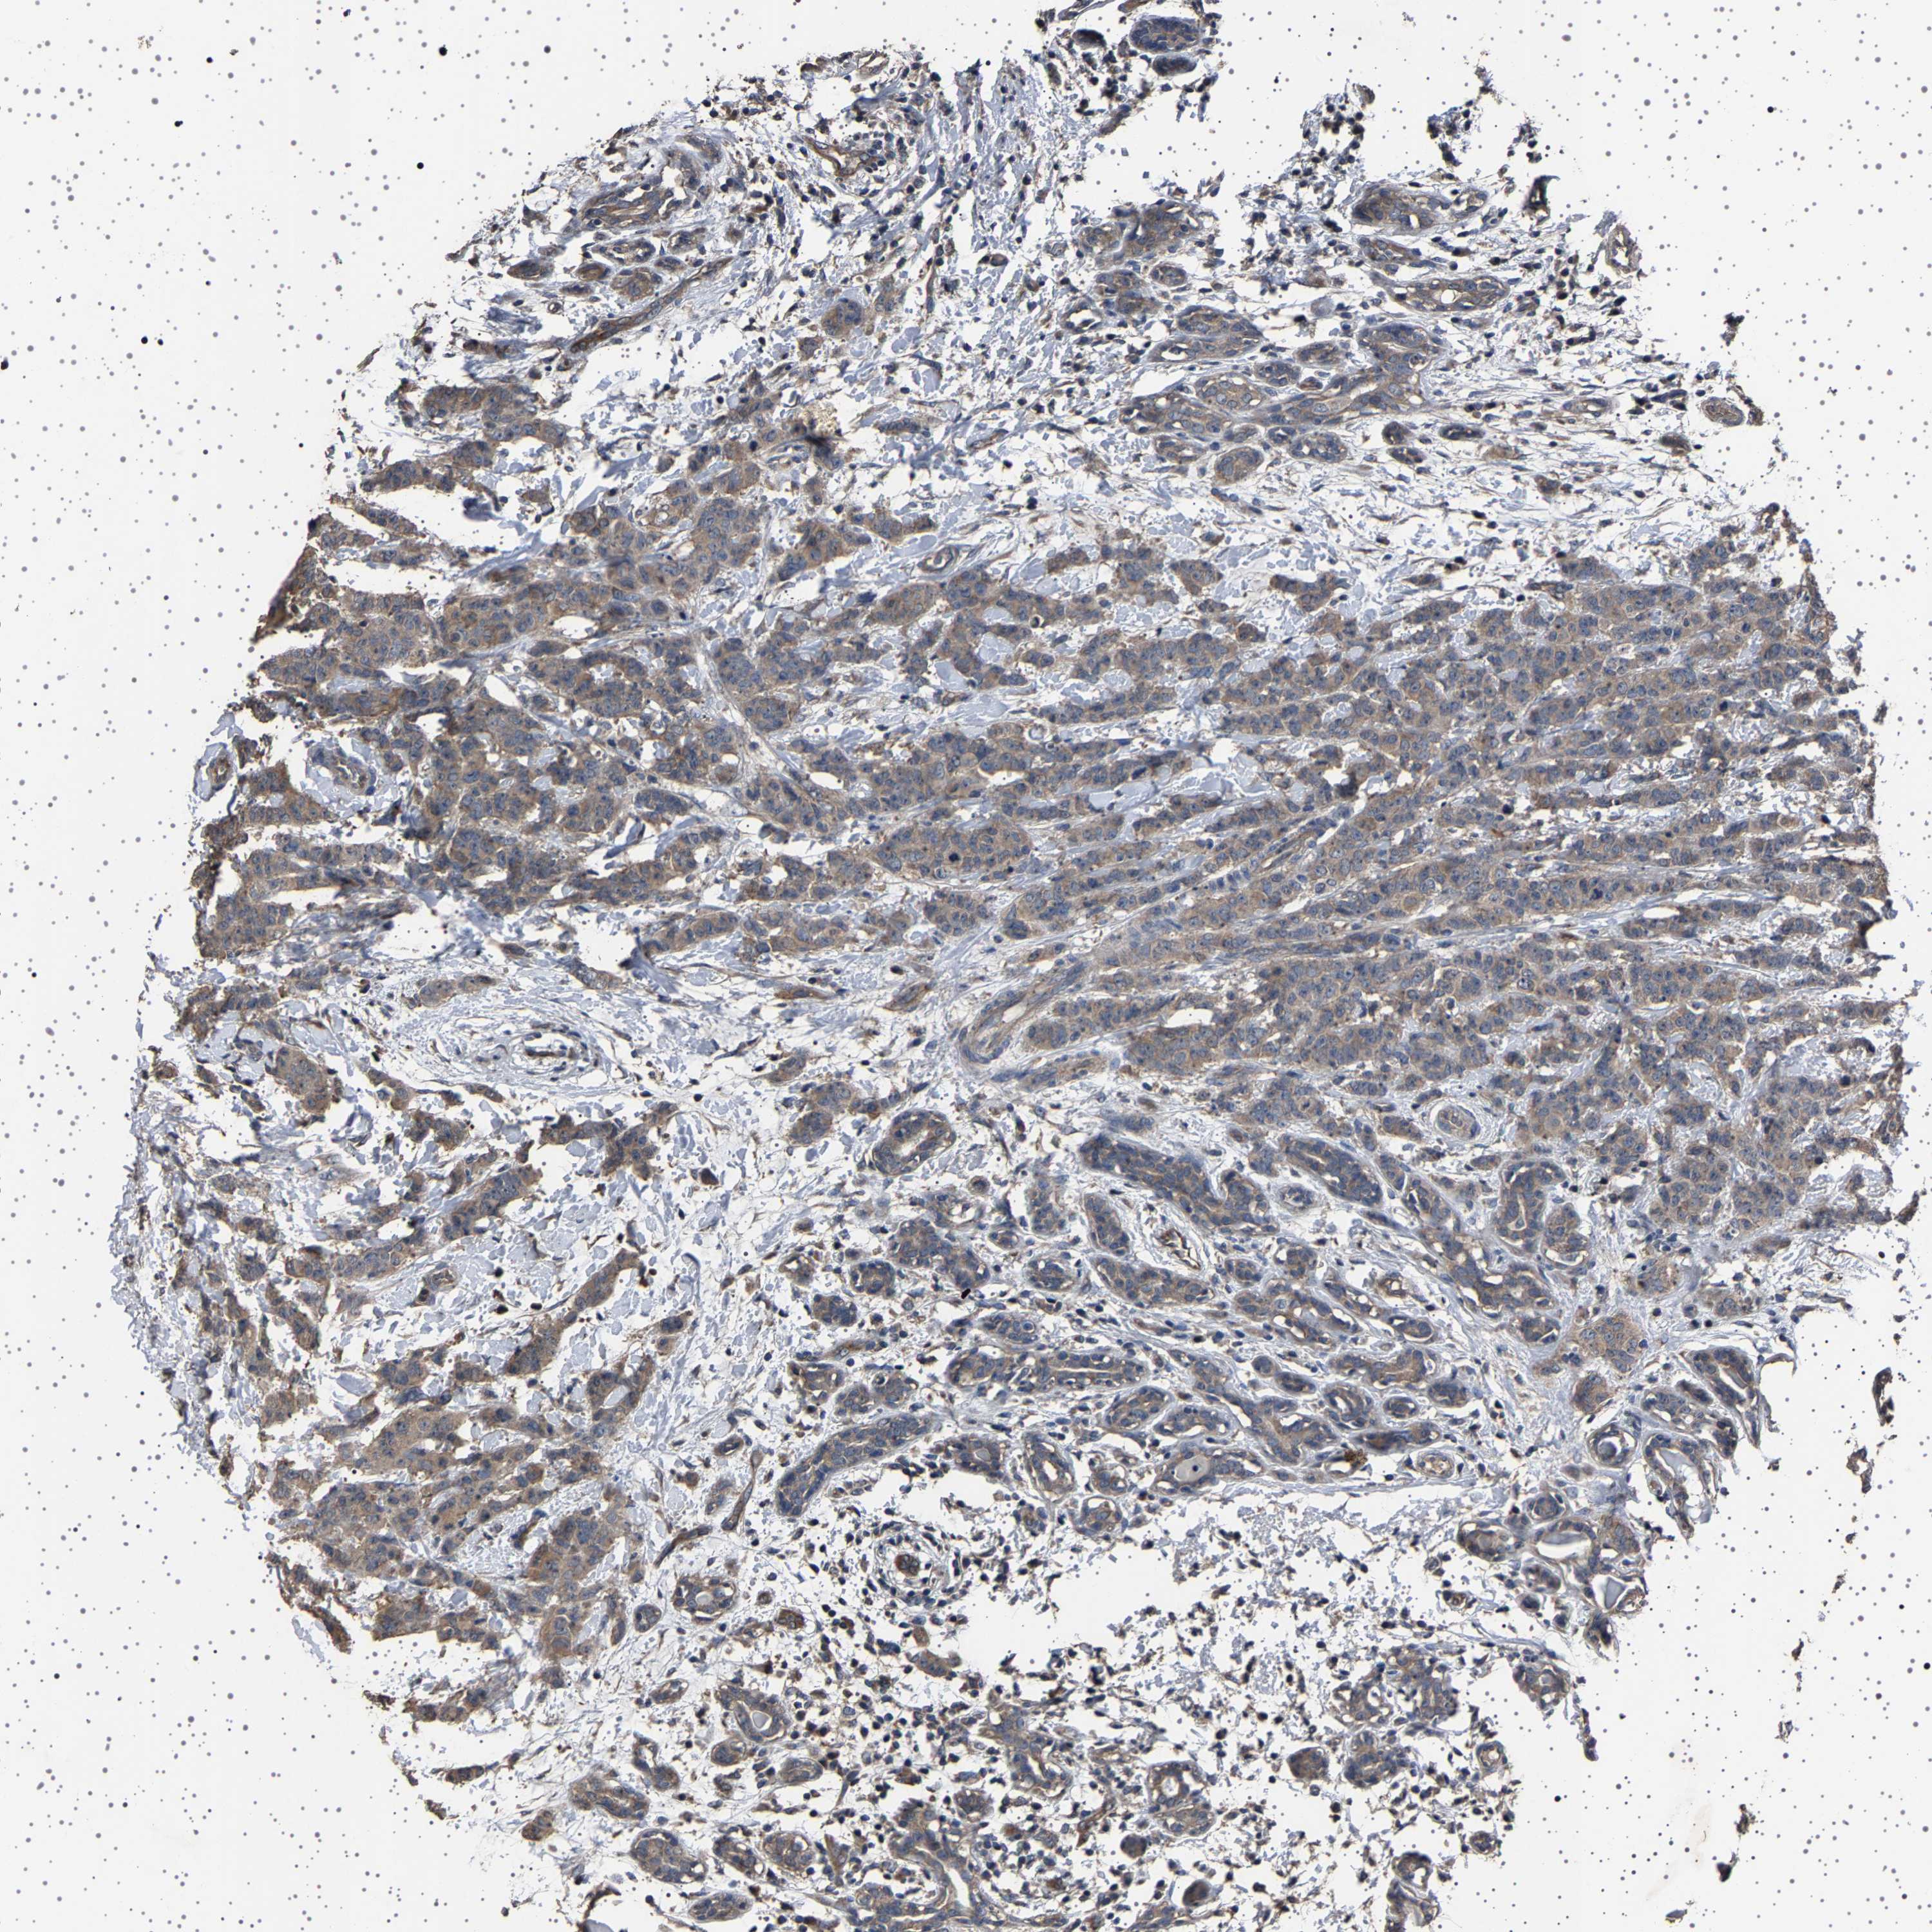

CANCER BREAST CANCER Show tissue menu

BRCA TCGA BRCA VALIDATION PROTEIN EXPRESSION